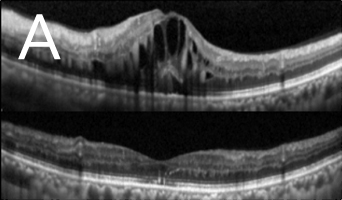

近視超過600度的人士眼球拉長的情況非常嚴重,黃斑點亦被拉扯變薄。再加上不正常的玻璃體和黃斑點視網膜前膜增生之牽引,導致黃斑點神經組織裂開,甚至喪失視力。如未能及早施行適當治療,黃斑點裂損有可能進一步惡化,導致黃斑點穿孔和黃斑點視網膜脫落。利用光相干性斷層造影可及早發現並作出準確的診斷(圖3)。治療方法是施行扁平部玻璃狀體切除術,移除凹前表質玻璃體,並進行氣體和液體交換,治療可治癒大部份病人的黃斑點凹位,而大部份病人在手術後亦無須保持俯臥。

![]() ![]() Photo 3: 圖3:光相干性斷層造影(OCT):(A)發現大量黃斑點裂損,並有視網膜黃斑點凹位脫落跡象,且在黃斑點凹位附近發現不正常的玻璃體牽引(箭頭所指位置)。(B)手術後六個月黃斑點裂損的情況大有改善,減少視網膜黃斑點脫落的幅度。 |